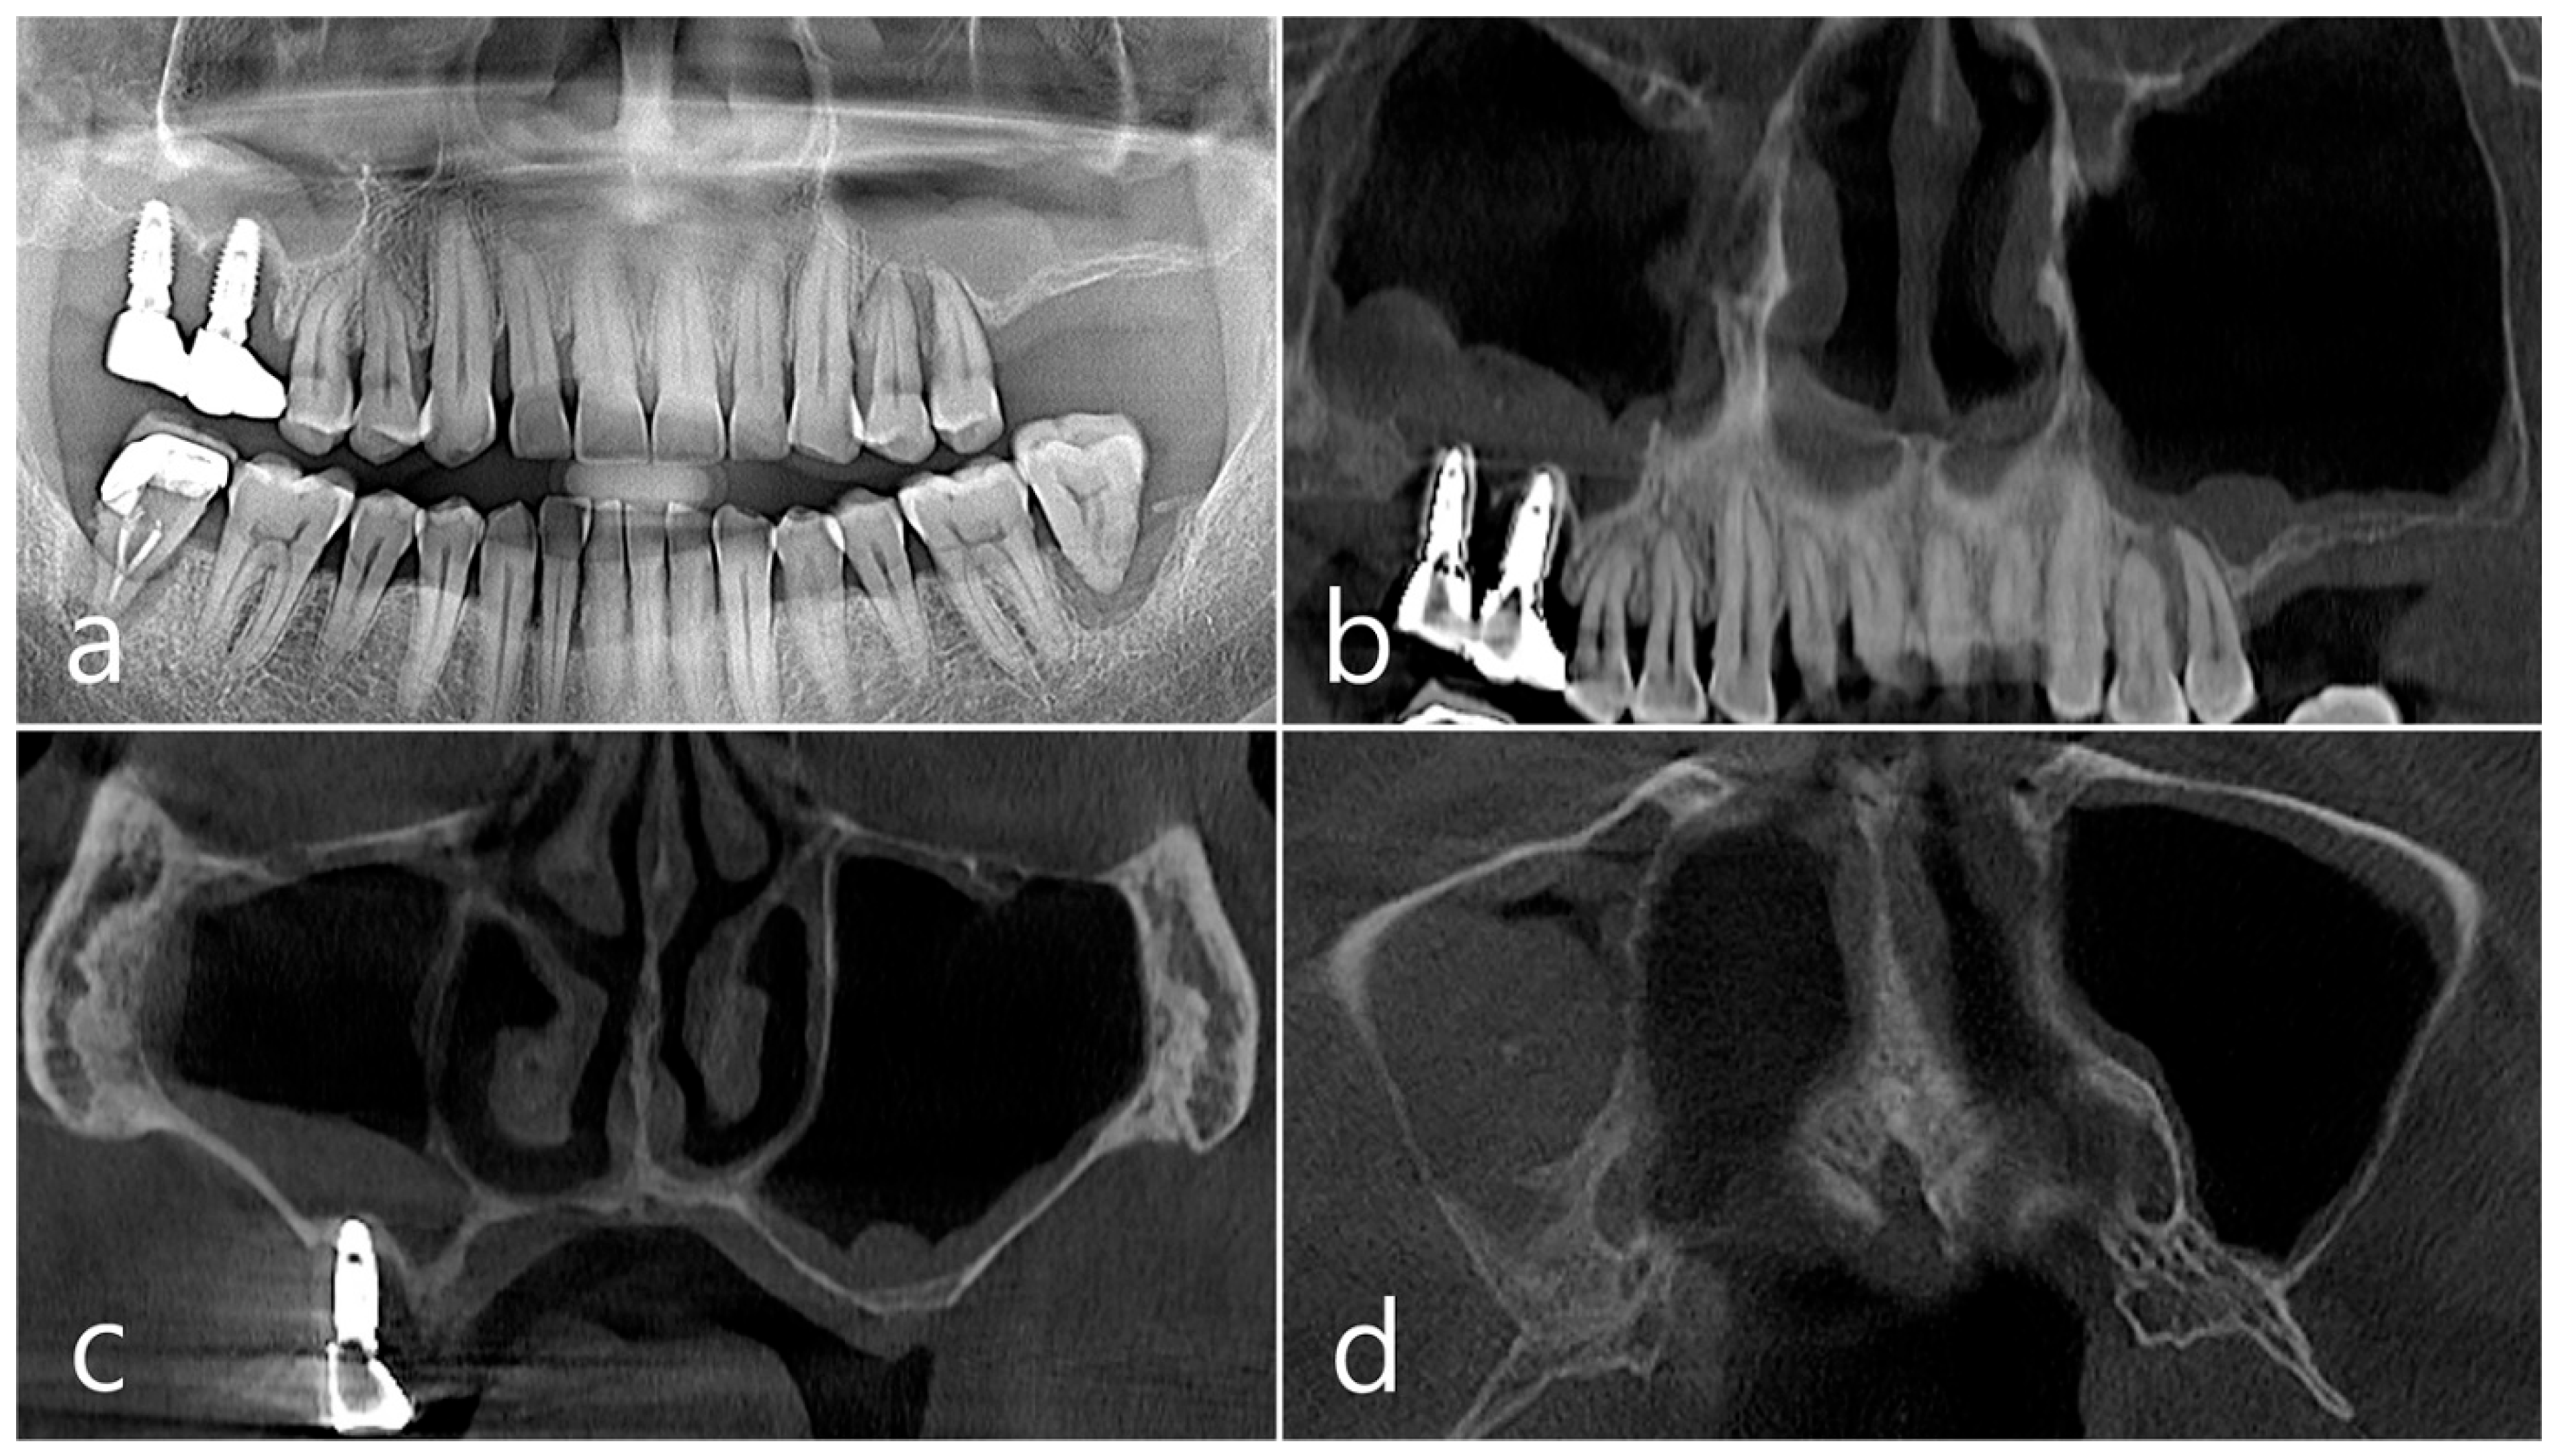

This patient, a 67-year-old female non-smoker, reported no systemic disease that could interfere with the operation. The patient visited the clinic for implant placement for the missing teeth. Panoramic radiography and CBCT were taken. On panoramic radiography, resorption of residual alveolar ridge and pneumatization of the maxillary sinus were observed in the left and right posterior region. Since the amount of residual alveolar bone was 4–6 mm in the maxillary right posterior region, a transcrestal sinus lift was planned (Figure 1a). In the preoperative panoramic, coronal, and axial images of the CBCT scan, abnormal images of the maxillary sinus were not observed, and there was no sinus membrane thickening (Figure 1b–d).

Figure 1. Case 1. (a) In panoramic radiography, resorption of residual alveolar ridge and pneumatization of the maxillary sinus were observed in the left and right maxillary posterior region; (bd) In preoperative CBCT’s panoramic, coronal, and axial images, there were no abnormal findings of the maxillary sinus and no sinus membrane thickening.